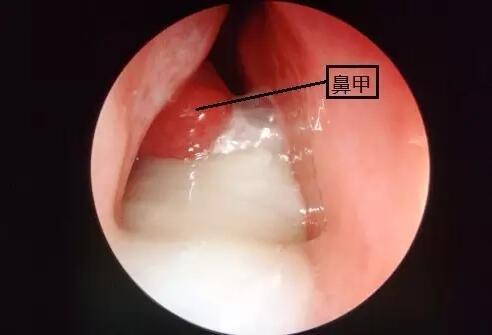

鼻甲红肿

鼻甲红肿,鼻甲肿胀

性鼻炎 症状:鼻塞(间歇性,交替性) 多涕 体征:鼻黏膜充血,下鼻甲肿大

鼻甲肿胀

鼻甲

鼻甲肥大

下鼻甲肥大

鼻甲肥大图片